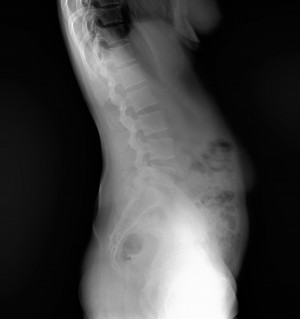

Western Australia, Australia Mar 18, 2021 (Issuewire.com) - Say goodbye to those long waiting times for full spine or leg length studies because within 1 second you can achieve a quick image acquisition with the Longtail – the latest innovative x-ray technology from ATX Medical Solutions. With over 30 years of experience, ATX Solutions has evolved with a profound knowledge of X-ray equipment and its services. The company takes pride in offering a high level of service with unlimited user support to ensure maximum benefits. Recently, a team of experts has initiated the use of this new digital X-ray equipment installed at Capital Radiology in Morley, Western Australia. Clients may ask for the relevance and importance of this newly installed system. Well, to answer their query, Regional Manager at Capital Radiology WA, Joel Scaddan, identified, 3 key features worth mentioning include the following:

- Accuracy – no overlapping errors or patient movement compared to other conventional ‘stitched’ systems; and

- Reduced dose compared with stitched systems – due to no overlapping of images and the removal of the anti-scatter grid depending on patient body habitus.

So, what does this all mean? In a nutshell, the Longtail digital radiography system delivers the highest image quality, geometric accuracy whilst reducing the amount of radiation with no image overlap received by the patient per diagnostic study. Moreover, practitioners will find it more convenient as they are now able to deliver swift diagnostic results. Managing Director Roger Davis commented the Longtail will supersede existing technologies for full spine imaging systems that are subject to excessive dose, multiple exposures, and software image adjustment techniques that may compromise the diagnosis.